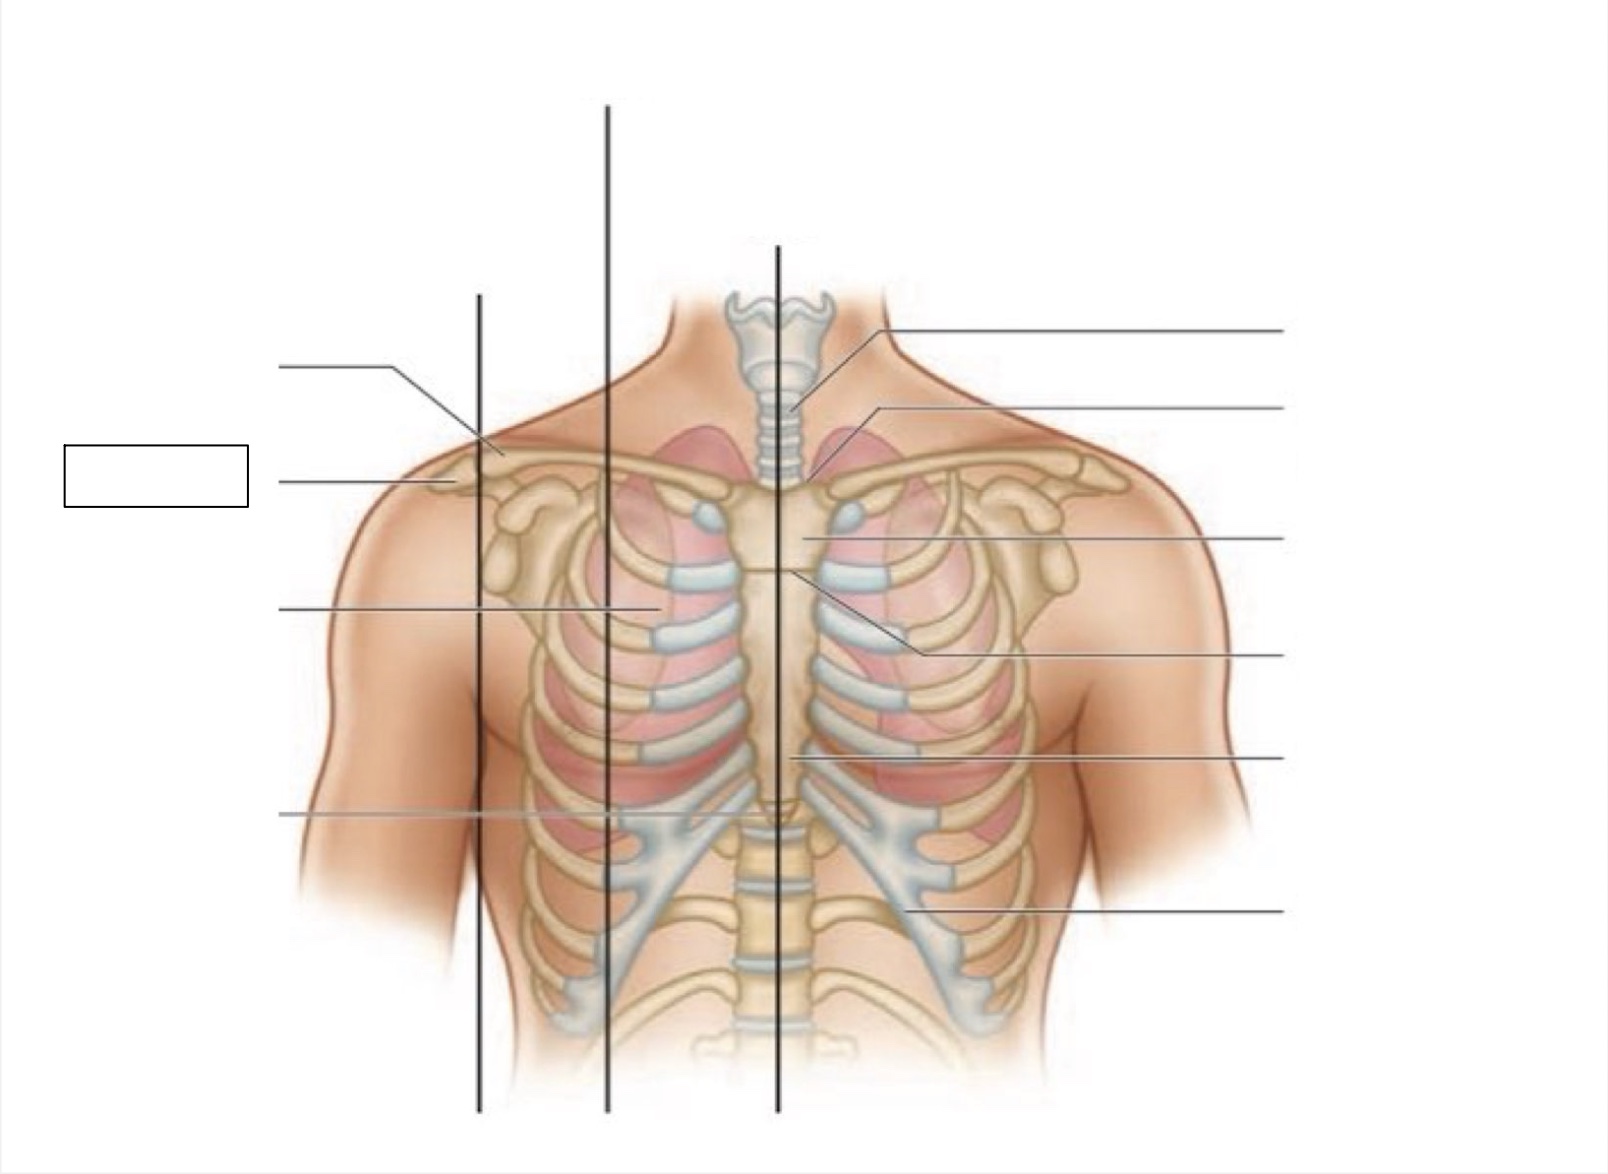

midsternal line

trachea

suprasternal notch

manubrium

angle of Louis

sternum

costal margin

xiphoid process

intercostal space

acromion

clavicle

anterior axillary line

midclavicular line

inferior angle of scapula

scapula

midscapular line

midspinal line

spinous process